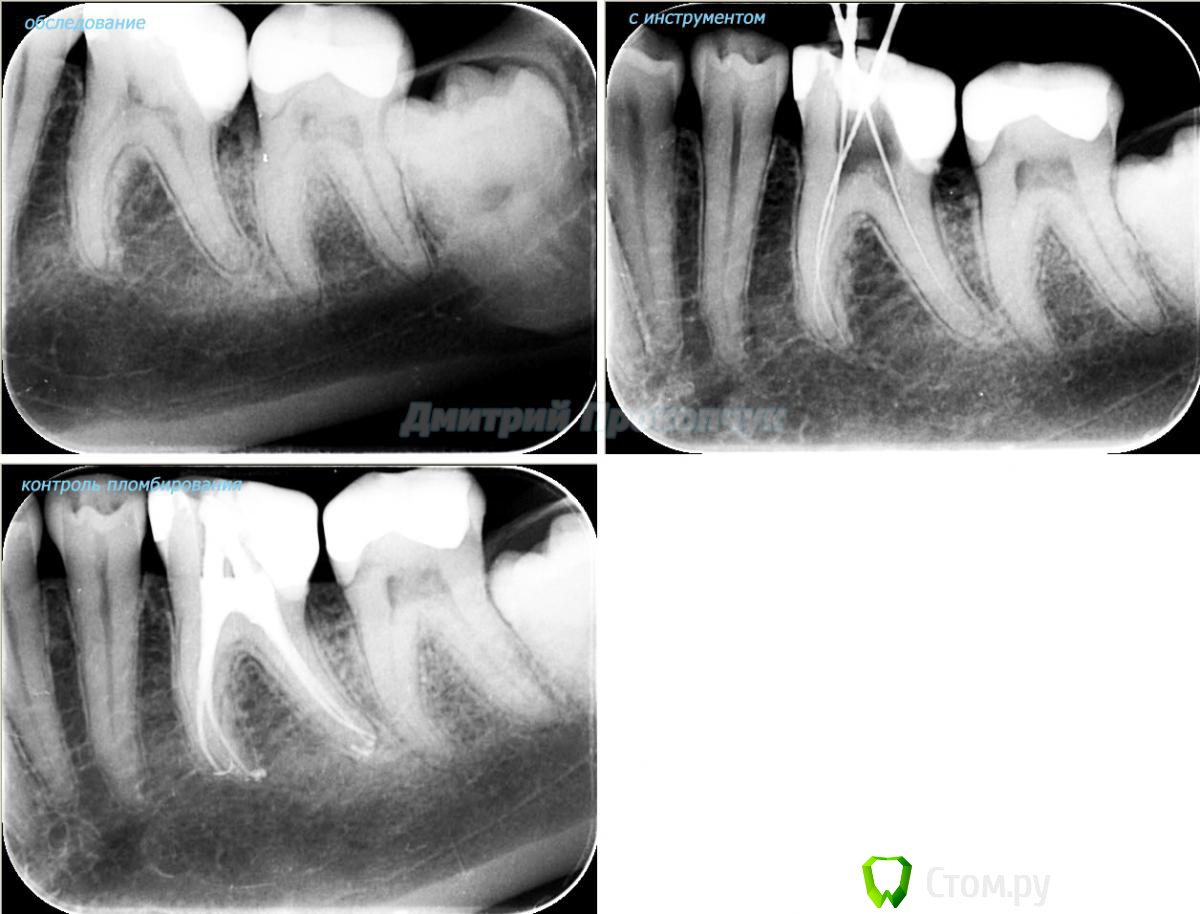

punkrat Опубликовано 16 сентября, 2014 Поделиться Опубликовано 16 сентября, 2014 Коллеги, тема , возможно, не имеет смысла просто приятная мне эндодонтия, сохранил с предыдущего места работы. Да, будь я проклят, я все знаю, НИГДЕ НЕТ КОФЕРА, на новом месте с этим норм. В общем если посчитаете, что я недостоин постить тут свои снимки, то так тому и быть, удалю тему.. 01. плановый ретрит 46ого и результат через 7 месяцев. Осложняющим моментом тут было то, что длина каналов была около 26 мм... 02. первичное эндо 34 (подготовка к ортопедии) + бонус - ретрит 35 03. ретрит 26 (подготовка к ортопедии) 04. ретрит 15, 16 (подготовка к ортопедии). основная сложность была в ретрите 15 - он был запломбирован термафилами, да еще снабжен свш... 05. ретрит 27 (подготовка к ортопедии). Ничего особенного, со временем посмотрим какова будет убыль этого совсем немаленького разрежения 06. ретрит 13. Разумеется пришлось выбивать вкладку, а потом еще попилить 3-4 миллиметра цемента, но, таки попилил куда нужно... 07. ретрит 17 (подготовка к ортопедии). В данном случае я, кажется, потратил больше времени на снятие литого моста, чем на лечение 17)) 08. ретрит 16 (подготовка к ортопедии). Снимка с инструментом нету, поскольку, визиограф сломался и его делал на пленку. 15 разумеется тоже перелечен... 09. плановый ретрит 16 10. первичное эндо 36, рядовой случай что дистальный щечный удалось найти не сразу, он был спрятан под нависающим дентиклем 11. ретрит 12, 11 (подготовка к ортопедии). Казалось бы, рядовой случай, если бы корневые каналы обоих зубов не были бы налухо забиты резорцин-формалиновой смесью... 12. ребенок 9ти лет, острый пульпит 46, попробовал оставить витальным. Пока полет нормальный, но даже если придется делать эндо в последствии, лучше когда оно будет сделано в более старшем возрасте... 13 Ссылка на комментарий